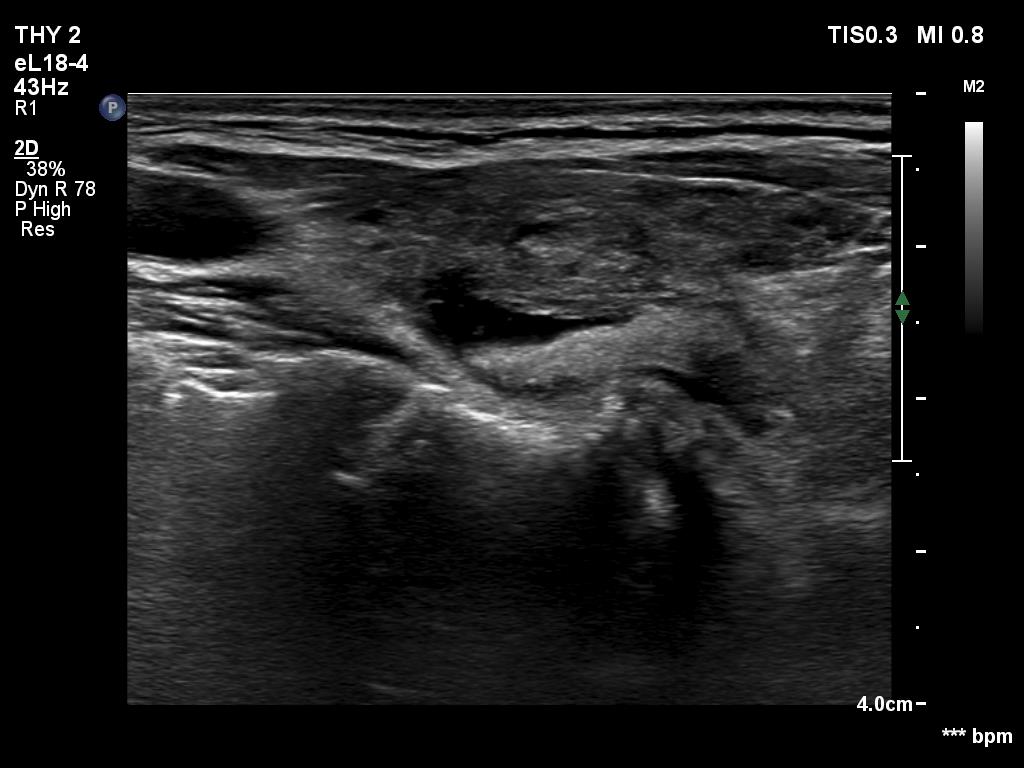

Ultrasonography. The thyroid was hypoechoic and presented several more hypoechoic and echonormal islets corresponding to the underlying thyroiditis. There was a mixed, dominantly cystic mass dorsal to the lower two-third of the right lobe. The lesion has echonormal solid part and showed intracystic echogenic figures.